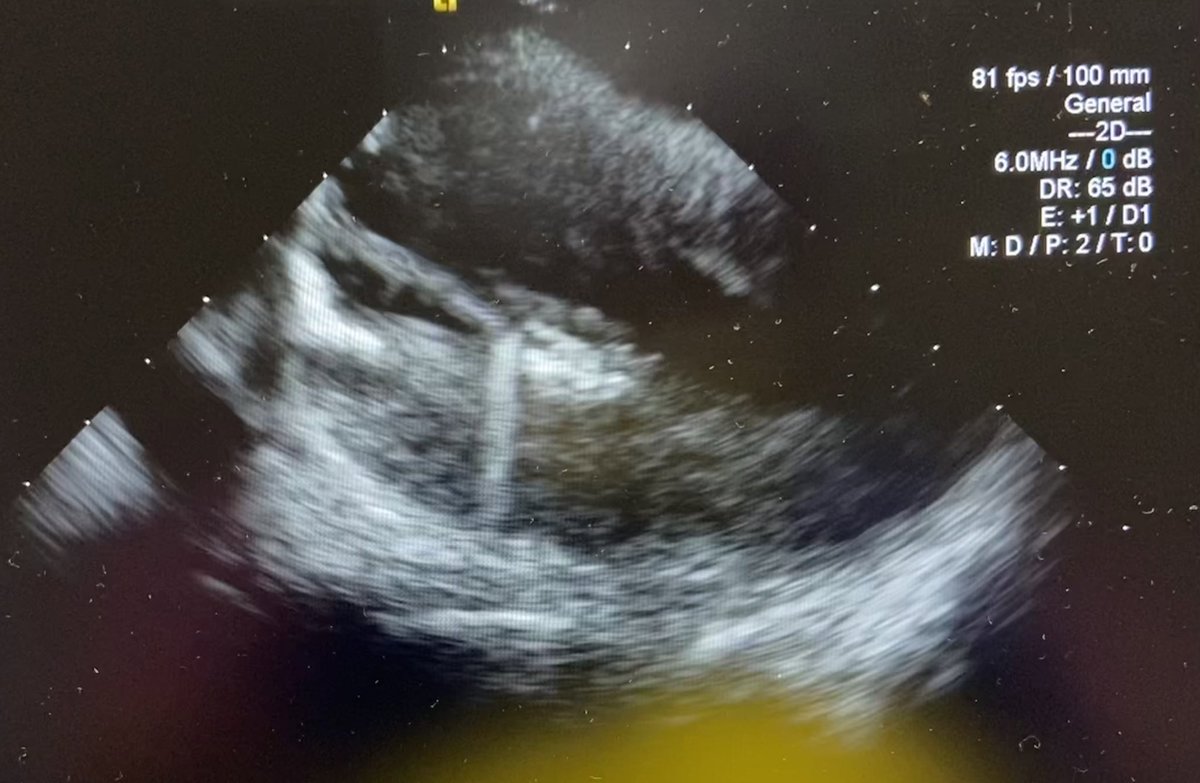

ICE imaging from left to right? Left sided ICE is a great way to visualize, not only the PVs and LAA, but also SVC and adjacent structures. #MapMoreBurnLess @AbbottCardio

JuanBurnTerm's tweet image. ICE imaging from left to right?

Left sided ICE is a great way to visualize, not only the PVs and LAA, but also SVC and adjacent structures.